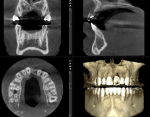

Additionally, a CBCT scan is paramount for proper 3-dimensional implant planning to determine the optimal bone grafting protocol and location for the implant and its proximity to adjacent teeth, and to evaluate the quantity and quality of the surrounding osseous foundation (Figure 14). Also, the surgeon should know at this point if the final restoration will be cemented or screw-retained, and any concerns should be addressed to avoid potential miscommunications regarding the final implant position and design for the final restoration. In this case the knife-edge ridge (Figure 4) was also corrected to provide a proper foundation for the implant (Figure 15). Due to an extreme deficient buccal concave contour on the maxillary right central incisor, the final contour of this tooth also had to be considered, as the adjacent edentulous area would need a bone graft to correct the edentulous knife-edge ridge, and the implant size and position and final crown contour would have to be evaluated (Figure 15 and Figure 16).